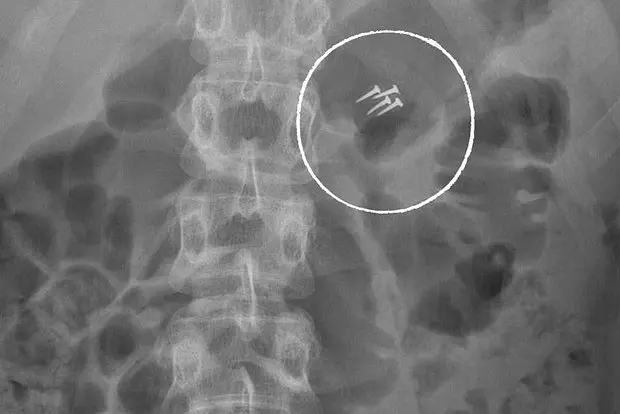

Среди изъятых объектов оказались беспроводные наушники, ювелирные украшения и даже строительные гвозди, случайно проглоченные мужчиной во время ремонтных работ. Каждый случай демонстрирует неожиданные бытовые ситуации, приводящие людей в операционные.